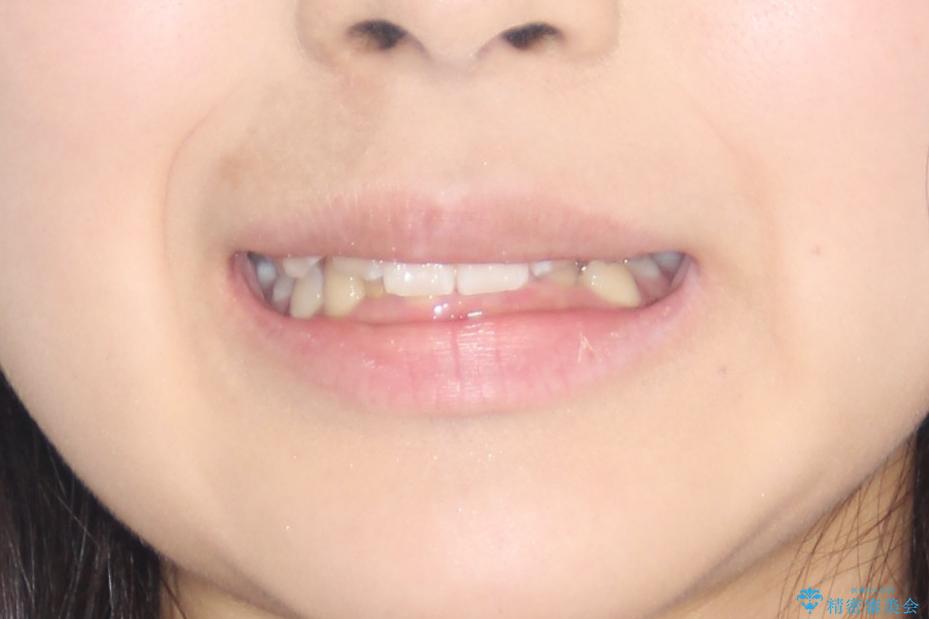

- 前歯の凸凹と深い噛み合わせを主訴に来院されました。

下の前歯が見えないほどのディープバイト症例でした。

下顎前歯も綺麗に見えるようになり大変満足していただきました。